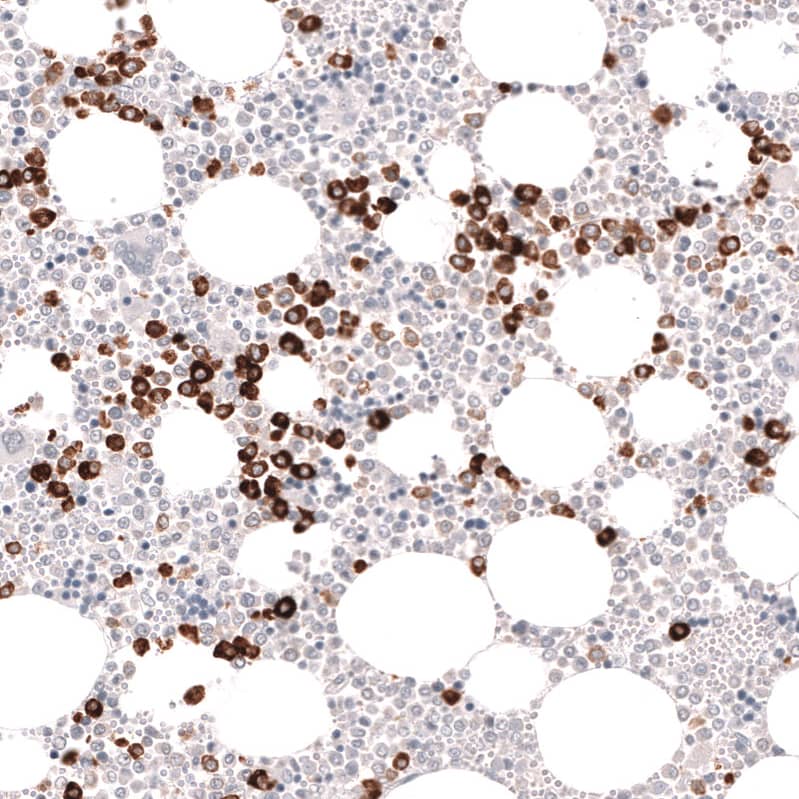

Staining of human bone shows strong cytoplasmic positivity in hematopoietic cells.

Orthogonal Strategies: Analysis in human bone marrow and skeletal muscle tissues using NBP3-44266 antibody. Corresponding Myeloperoxidase/MPO RNA-seq data are presented for the same tissues.